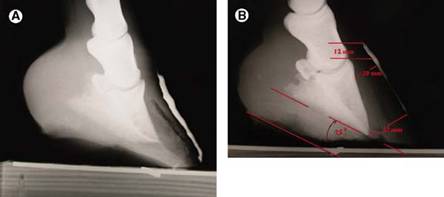

Dermos ir rago plotis gali būti išmatuotas, panaudojant kanopos ir pado sieneles. Nustatant dorsalinės kanopos sienos išorinį paviršių yra naudojama bario pasta, kuria tepamas kanopos paviršius, pradedant nuo proksimalinio paviršiaus ir leidžiantis žemyn (2 pav.). Apatinį pavir 333h77d šių apriboja pasaga ar pakeliamasis blokas. Padarius rengenogramą, išmatuojami atstumai (1 pav.).

1 pav. Vaizdas, leidžiantis tiksliai išmatuoti reikalingus rentgenologinius matmenis (Redden R.F., 2003)

2 pav Minkštųjų audinių rentgenogramai atlikti, kanopos pakeliama nuo žemės (Redden R.F., 2003)

Pado gylis paprastai matuojamas trečiojo pirštakaulio distaliniame gale arba jo viršūnėje (1 pav). Sveikos kanopos pado gylis yra mažiausiai 15 mm. Venografiniais tyrimais nustatyta, kad jei pado gylis yra mažesnis, tai iššaukia klinikinius požymius. Normaliam vystymuisi, pado dermos speneliams reikia 10 mm tarpo tarp trečiojo pirštakaulio palmarinio paviršiaus ir raginio sluoksnio, kad ten tilpų kraujagyslės ir, mažiausiai 5 mm tarpo nuo pado rago, kad pado derma būtų apsaugota. Arklių, kurių pado gylis nesiekia 15 mm, venogramose matomi sulinkę, suspausti speneliai arba jų iš viso nėra. Ši deformacija ar suspaudimas slopina pado augimą, sukelia silpno, plono pado rago formavimąsi (Redden R.F., 2003) .

Dorsalinės rago-lapelių zonos plotis – tai atstumas tarp trečiojo pirštakaulio dorsalinio paviršiaus ir išorinės dorsalinės kanopos sienos (matuojama su liniuote, statmenai trečiojo pirštakaulio dorsaliniam paviršiui) (1 pav). Dorsalinės rago-lapelių zonos plotis gali būti matuojamas bet kurioje trečiojo pirštakaulio dorsalinio paviršiaus vietoje, tačiau dažniausiai matuojama šiek tiek žemiau proc.extensor ir netoli trečiojo pirštakaulio distalinės viršūnės (Redden R.F., 2003).

Atstumas tarp vainikinės ir tiesiamosios ataugų - tai vertikalus atstumas tarp proksimaliausio išorinės kanopos sienos taško (iš kart po vainikiniu raiščiu) ir trečiojo pirštakaulio proc.extensor viršaus (1 pav.).

Esant sveikai kanopai, šis rodiklis svyruoja 0-15 mm ribose. Tai svarbu nustatant trečiojo pirštakaulio poslinkį, siekiant ligą diagnozuoti dar neklinikinėje stadijoje ar pačioje jos pradžioje (Redden R.F., 2003).